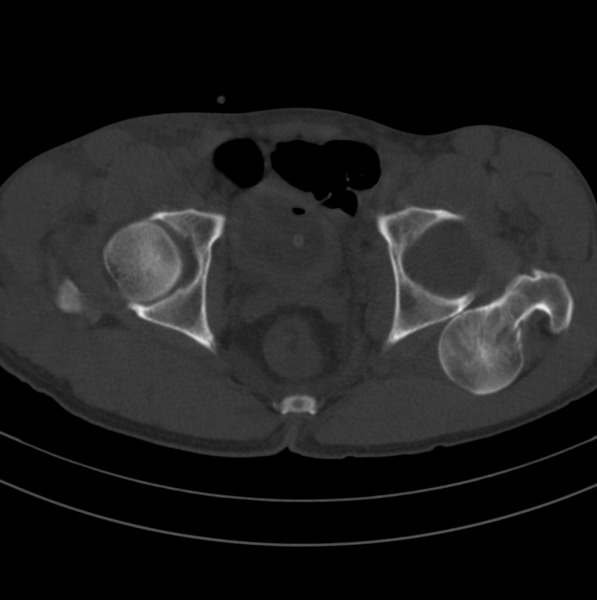

标题: CT18589:股骨头囊状阴影怎么下结论?

男、53

股骨头内的囊状阴影怎么下结论?

1.左髋后脱位。

髋关节脱位、股骨头疝窝。

左侧髋关节后脱位;左侧股骨头疝窝。

股骨颈疝窝是发生于股骨头基底和股骨颈的一种较少见的良性病变。发病率约在4% 一5% ,好发于中老年人,多无明显症状,常因其他病变检查时偶然发现 。病变多单侧发生,少数为双侧。影像学的正确诊断,可避免不必要的外科手术。

x线平片和ct上多表现为位于股骨头基底和股骨颈近段前侧皮质下、股骨颈中轴线外侧的圆形或卵圆形透亮区或软组织密度灶,边界清楚,多伴有薄层硬化缘。病灶最大径线通常<10 mm。病灶或相邻上下层面上相邻皮质大多可见与病灶相连的局限性裂隙样缺损,可作为诊断此病的特异性征象。病灶内通常为纤维结缔组织和(或)液体。内为液体时,病灶呈均匀长t1、长t2信号。纤维结缔组织和液体同时存在时,病灶于t1wi上呈低信号,t2 wi上呈不均匀高信号。